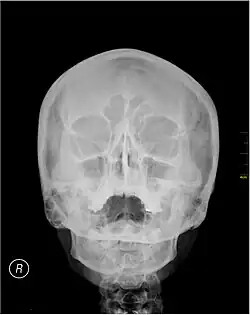

Waters' view

Waters' view (also known as the occipitomental view or parietoacanthial projection) is a radiographic view of the skull. It is commonly used to get a better view of the maxillary sinuses. An x-ray beam is angled at 45° to the orbitomeatal line. The rays pass from behind the head and are perpendicular to the radiographic plate. Another variation of the waters places the orbitomeatal line at a 37° angle to the image receptor. It is named after the American radiologist Charles Alexander Waters.

Waters' view can be used to best visualise a number of structures in the skull.

- Maxillary sinuses.

- Frontal sinuses, seen with an oblique view.

- Ethmoidal cells.

- Sphenoid sinus, seen through the open mouth.

- Odontoid process, where if it is just below the mentum, it confirms adequate extension of the head.

The Waters' view may not show the frontal sinus in detail.[1]

Typically, the x-ray beam is angled at 45° to the orbitomeatal line.[3] Another variation of the waters places the orbitomeatal line at a 37° angle to the image receptor,[4] or 30°.[5]